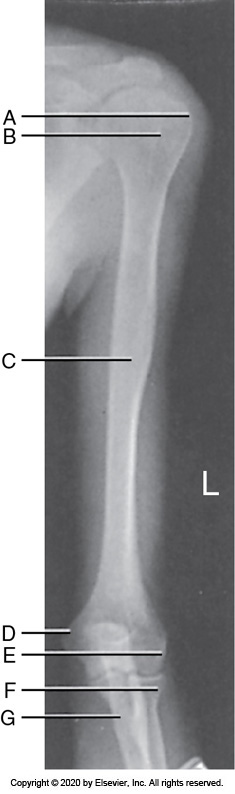

Identify the labeled anatomy "B" in the image below:

Radial styloid

An AP forearm projection with accurate positioning demonstrate the

1, 2, and 4 only